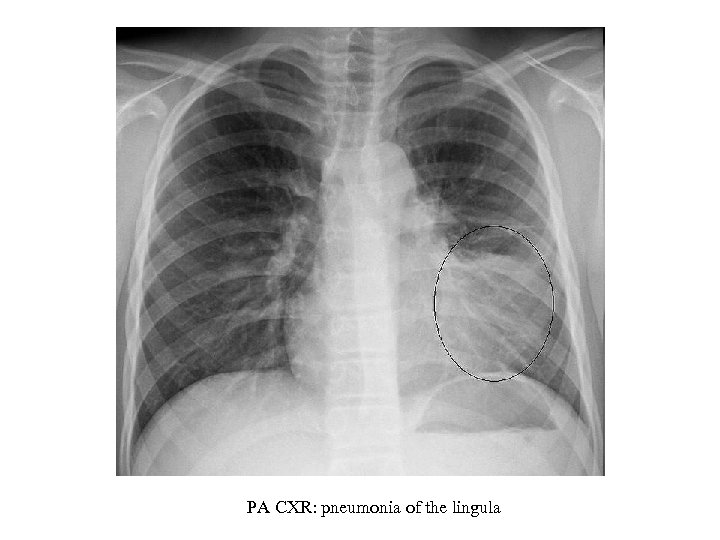

PA CXR: pneumonia of the lingula